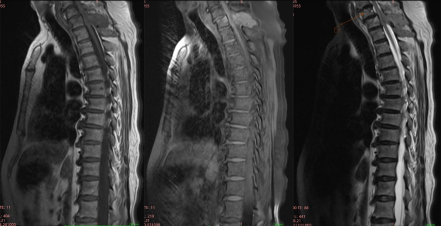

图6.L1-2水平髓外硬膜下神经鞘瘤MRI图像

图7.胸椎髓外硬膜下脊膜瘤MRI图像